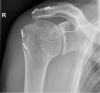

Isolated deltoid paralysis is a rare pathology that can occur after axillary nerve injury due to shoulder trauma or infection. This condition leads to loss of deltoid function that can cause glenohumeral instability and inferior subluxation, resulting in rotator cuff muscle fatigue and pain. To establish dynamic glenohumeral stability, a novel technique was invented. Humeral suspension is achieved using a double button implant with non-resorbable high strength cords between the acromion and humeral head. This novel technique was used in two patients with isolated deltoid paralysis due to axillary nerve injury. The results indicate that the humeral suspension technique is a method that supports centralizing the humeral head and simultaneously dynamically stabilizes the glenohumeral joint. This approach yielded high patient satisfaction and reduced pain. Glenohumeral alignment was improved and remained intact 5 years postoperative. The humeral suspension technique is a promising surgical method for subluxated glenohumeral joint instability due to isolated deltoid paralysis.